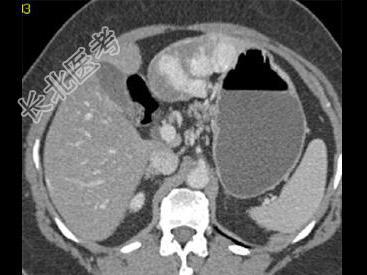

单项选择题根据所提供的图像,最可能的诊断是 ( )

A、肝癌

B、局灶性结节增生

C、血管瘤

D、胆管癌

E、以上都不是